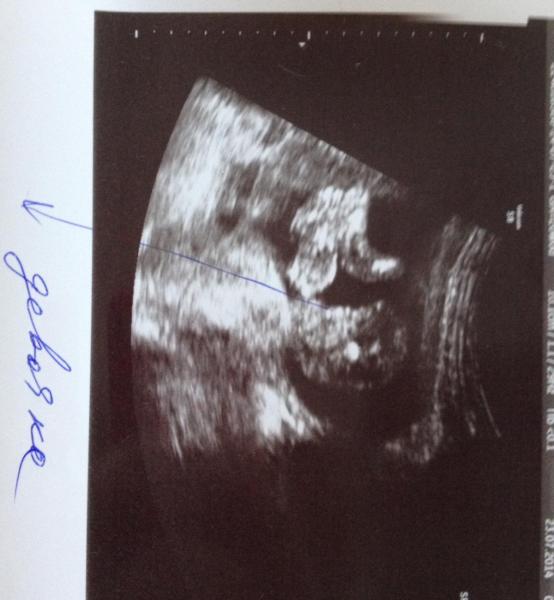

Aksy_aksy 143 Опубликовано: 16 августа 2014 Рассказать Опубликовано: 16 августа 2014 У нас вроде уже точно должна быть девочка) Колесникова сказала 100%, да я и не виду никаких мальчишичьих выпуклостей)У меня тоже такие снимки, и колесникова на 18 неделе ещё сказала тоже точно что девочка, я ещё переспросила на всякий случай))) но по этим снимочкам я если честно ничего не понимаю) а по моему все понятно) она лежит в позе эмбриона, попа смотрит на нас и две ступни, видно что белая точка это копчик ну а рядом все девичьи достоинства))) Нам когда дали снимки мы тоже ничего не понимали, пока я не додумалась что его надо перевернуть вертикально))) Ссылка на сообщение Поделиться на других сайтах